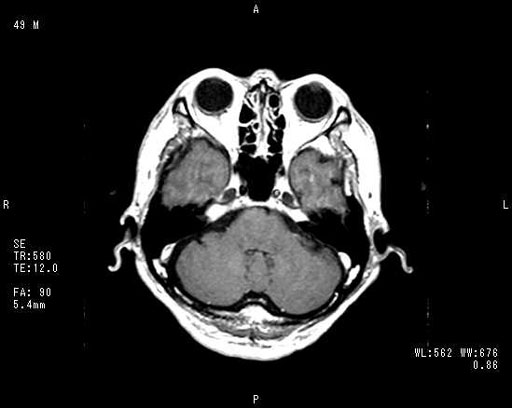

症例1:49歳,男性

右半身しびれ,構音障害

2日前より右手の軽いしびれがあった.

その後,右半身へしびれが広がり,構音障害も出現するようになったため当院受診となった.

図3a 造影T1強調横断像